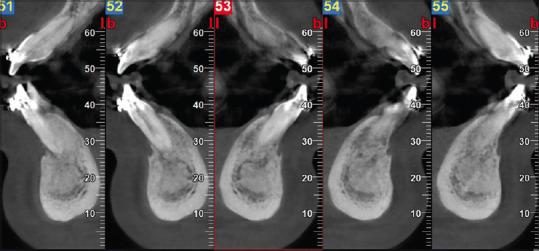

Gingival abscess is a localized, acute inflammatory lesion which is caused by various factors that include microbial plaque infection, foreign body impaction, and trauma. Management includes a simple incision and draining of the purulent exudate along with systemic antibiotics in most of the cases. This article reports a case of a 16-year-old female patient, with a chief complaint of painful and swollen gums in her lower right front tooth region of the jaw along with fever for the past 5 days. Emergency treatment of abscess drainage was done on day 1. On 5 day of review, the case presented with persistent signs of gingival inflammation in relation to 43 to 41. Considering the provisional diagnosis as dentigerous cyst with persistent gingival abscess, definitive treatment was performed by transalveolar extraction of the impacted canine and debridement of the osseous lesion. The histologic analysis of the lesion exhibited foci of eosinophilic coagulum-like areas with epicentric and radiating filamentous appearance at the periphery, which is suggestive of an inflamed dentigerous cyst with actinomycosis infection of periodontium.

牙龈脓肿是一种局限性急性炎症性病变,由多种因素引起,包括微生物菌斑感染、异物嵌塞和创伤。在大多数情况下,治疗包括简单的切开引流脓性渗出物以及全身性使用抗生素。本文报告了一例16岁女性患者,主要症状为下颌右下前牙区牙龈疼痛肿胀,伴有发热5天。第1天进行了脓肿引流的急诊治疗。复查第5天时,43至41区域仍有持续性牙龈炎症迹象。考虑初步诊断为含牙囊肿伴持续性牙龈脓肿,通过经牙槽拔除阻生尖牙并清除骨病变进行了确定性治疗。病变的组织学分析显示有嗜酸性凝块样区域,周边有中心和放射状丝状外观,提示为伴有放线菌感染的牙周炎的含牙囊肿炎症。